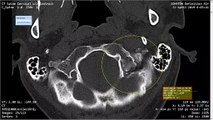

4/22/19 Broken Skull CT Scan Misdagnosis Bill

St. Vincent's East Cropped My Head CT And Cut Out Broken Skull Part 2

Found A Wulf / Botfly / Insect In My X-Ray / CT / MRI - Misdiagnosis!